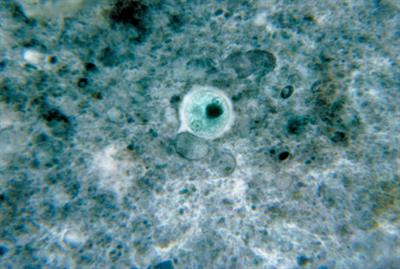

Cyst stage of Entamoeba histolytica